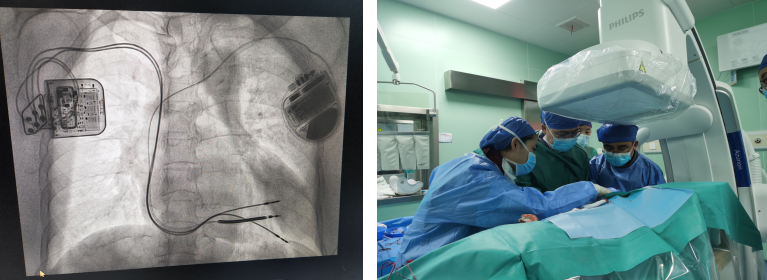

日前,山东大学齐鲁医院(青岛)心内科成功为一位既往植入埋藏式心脏转复除颤器(ICD)的重度心衰患者实施了心脏收缩力调节器(CCM)植入手术,这是我院近期开展的第二例CMM植入手术,也是山东省首例ICD术后联合植入CCM手术,标志着我院心内科在心血管介入诊疗技术方面再上新台阶。心衰诊疗技术的新突破,也为心衰患者带来“心”希望。

患者入院后,我院心血管中心常务副主任、心内科主任钟敬泉教授组织科内讨论,详细复盘患者病情后,医生团队认为,患者心力衰竭,EF值28%,QRS波仅为115ms,具备CCM植入指征。但患者既往ICD植入术后,心腔内存在一根电极,需要在心腔内额外植入两根电极,且彼此间距不能小于2cm,才能确保ICD和CCM正常感知与起搏,避免相互信号干扰;精准放置电极导线对此次手术尤为关键,也是手术的难点。

患者及家属充分知情后同意行CCM,在钟敬泉教授,心内科副主任姚桂华教授、由倍安教授指导下,心内科王守东副主任医师带领起搏电生理亚专业团队为该患者进行CCM的植入,该台手术局麻下患者全程清醒,术中精准置入电极并进行ICD与CCM的联合程控,保证参数良好,手术历时约1小时。术后次日为患者再次检查心脏超声,结果提示EF值已经升至38%,患者症状明显好转,术后3天顺利出院。